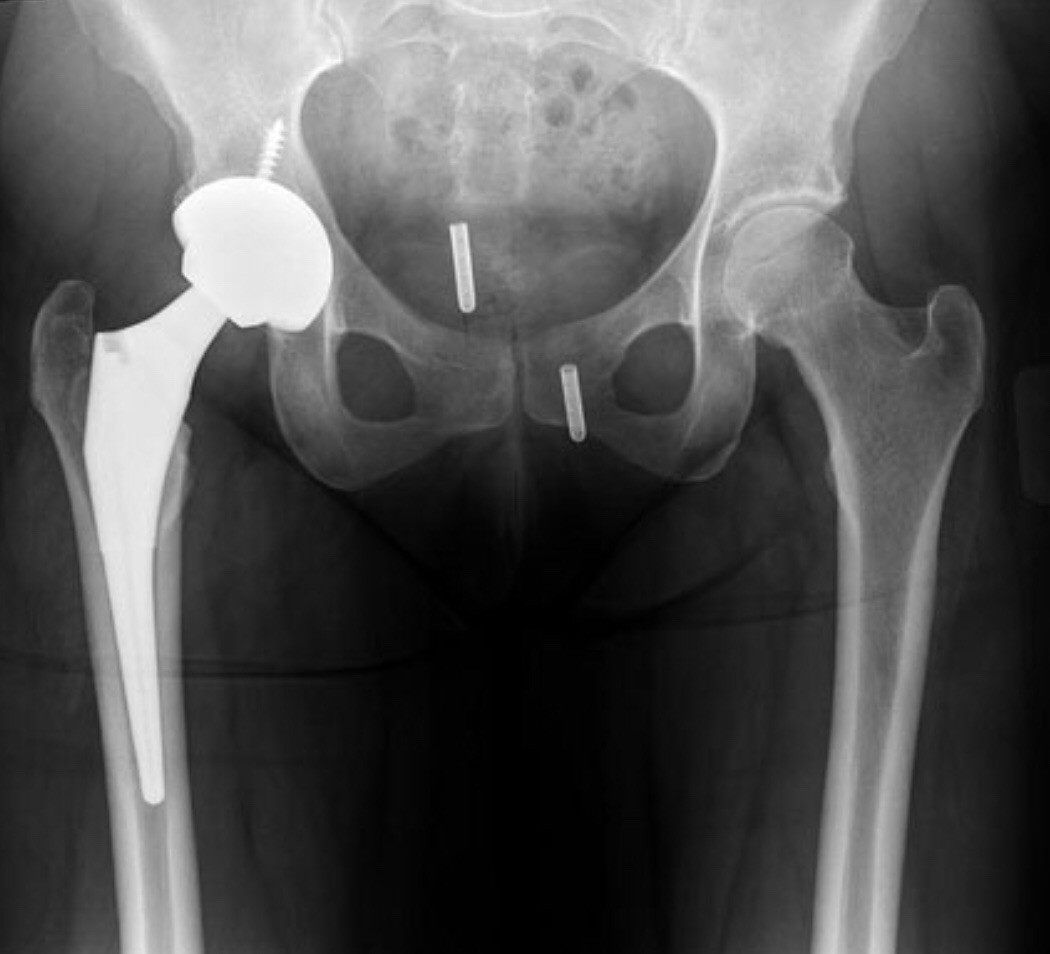

Пластина шейки бедра

Пластина шейки бедра 108 фото